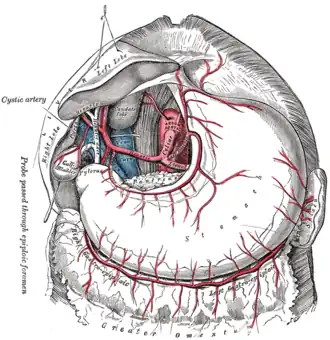

The celiac artery and its branches. | |

Branches of the celiac artery. The gastroduodenal artery appears on the left part of the figure and overlays/is anterior to the portal vein. The stomach is raised and inverted - compare with celiac artery branches - stomach in situ. | |